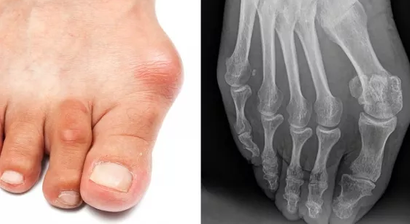

Fußchirurgie

Ich habe mich innerhalb meines Fachgebietes auf den künstlichen Gelenkersatz von Hüft- und Kniegelenk, arthroskopische Eingriffe sowie die Fuß- und Handchirurgie spezialisiert. Natürlich biete ich meinen Patienten darüber hinaus auch alle weiteren Leistungen der modernen Orthopädie an.